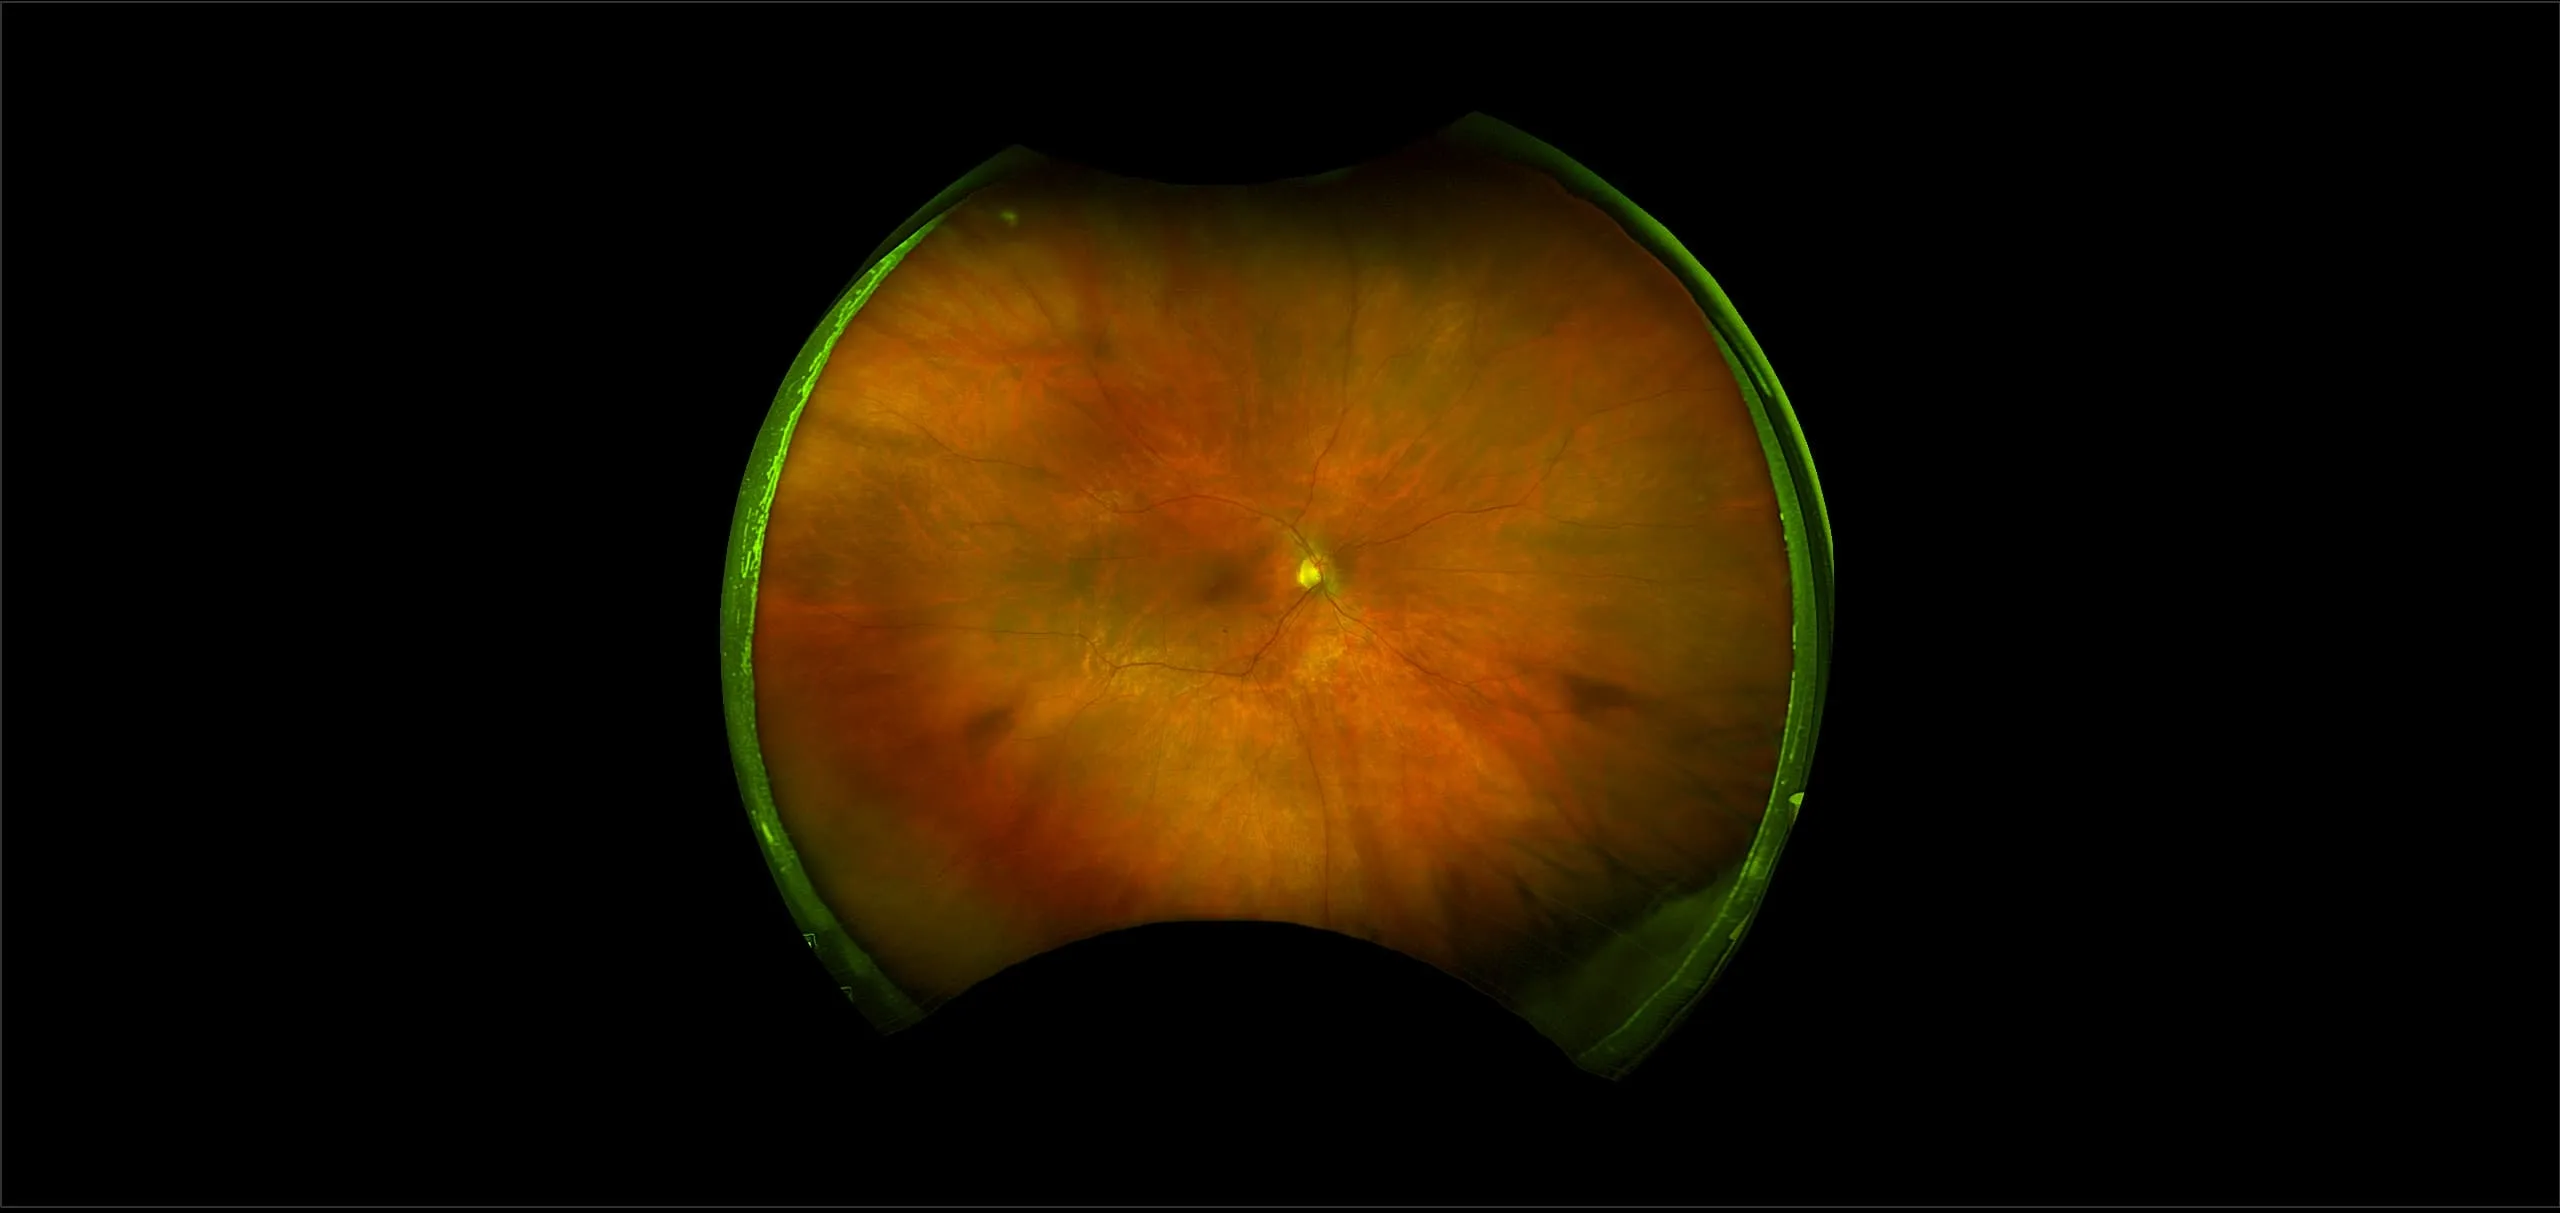

California - Laser Demarcated Retinal Detachment - Montage, RG, RGB

A retinal detachment (RD) is the separation of the sensory retina from the Retinal Pigment Epithelium (RPE) (outer segments of the photoreceptors from the microvilli of the RPE). Some times the retinal vessels on the detachment will be dark in appearance, as seen in a retinoschisis. This is likely due to the vessels blocking the exiting light. The appearance in a fresh detachment is of a white membrane, with tiny folds and blood vessels, in the vitreous cavity that moves (undulates) on eye movements. Because the outer surface of the detached retina is irregular (dangling outer layer segments) it will scatter light and this is what makes a fresh RD look white when using white light instruments to view it. With optomap, the green light is scattered more; thus, causing the detached retina to have a green appearance when elevated into the vitreous cavity. The underlying choroidal detail will be obscured by the scattering of the light (same with a retinoschisis but more prominent). Obscuration of choroidal detail is seen better on the red laser separation. The most common reason for a RD is a retinal tear and the most common reason for a tear is a PVD. Tearing of the retina may produce retinal or vitreous hemorrhages. Almost all clinically significant RDs (greater than 2 Disc Diameters (DD) from the edge of the break or 1 DD posterior to the equator) if left untreated will eventually lead to a blind eye, therefore, they are always treated.